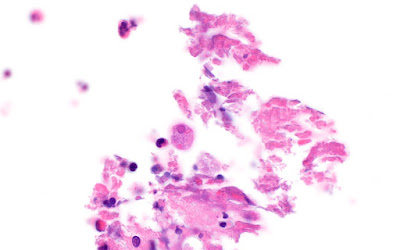

This week's case is from Dr. Steven Ruhoy and Tracie Rose. The patient is an elderly woman with a very itchy rash which is worse at night. The family practitioner noted excoriations on the plantar aspect, but did not see any definitive burrows. She performed a skin scraping which revealed the following on H&E-stained histologic section. What is your identification?

Answer to the Parasite Case of the Week 794: Winged insect, likely contaminant.

Many of you asked if this could be Pediculus humanus - a thought that I also initially shared. However, Blaine Mathison nicely pointed out that this insect has a wing, which rules out lice, as they are wingless. Here is his annotated image:

Based on this finding, it is likely that this is just a contaminant or inconsequential finding. It doesn't explain the patient's symptoms, and therefore further investigation is warranted.